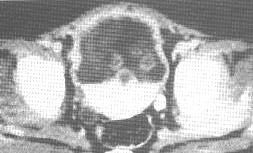

MRI

表現為T1加權像中等信號和T2加權像中等度增高的信號,信號程度不均,形態學上病灶可以邊界清或不清,但與其他軟組織腫瘤較難區別。